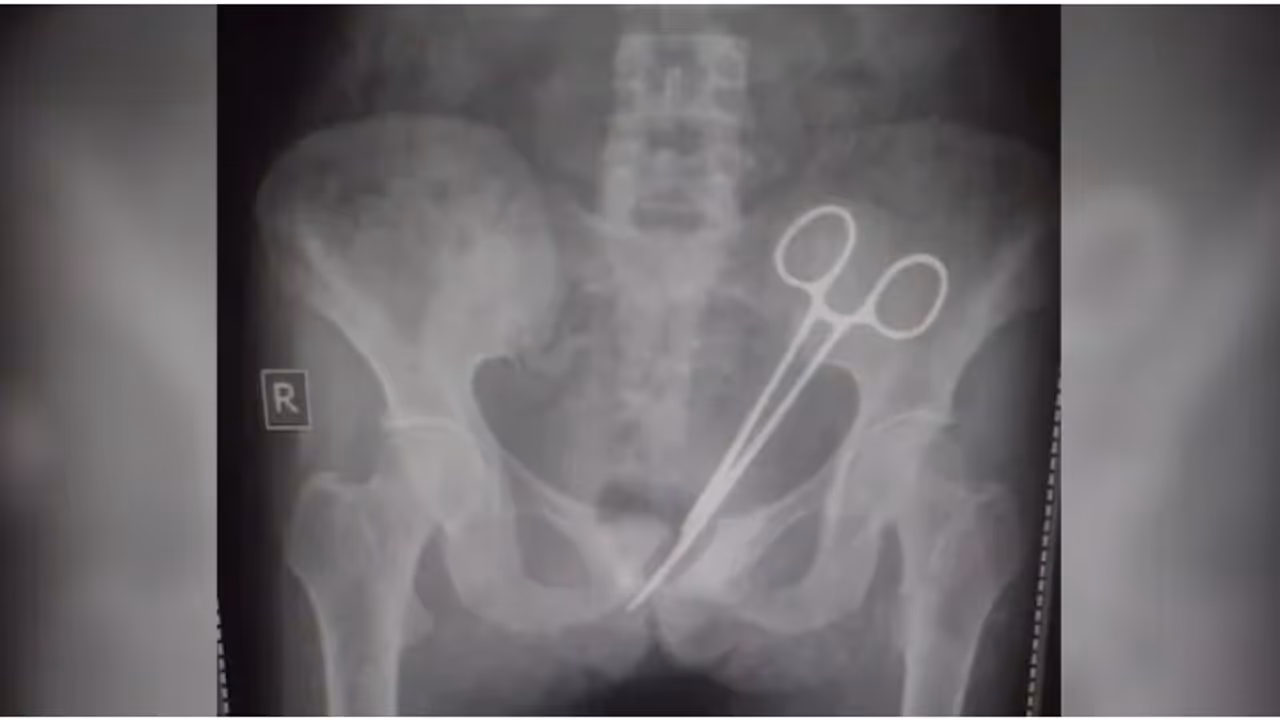

ആലപ്പുഴ വണ്ടാനം മെഡിക്കൽ കോളേജിൽ ശസ്ത്രക്രിയക്കിടെ രോഗിയുടെ വയറ്റിൽ കത്രിക കുടുങ്ങിയ സംഭവത്തിൽ ഡോക്ടർക്ക് വീഴ്ച പറ്റിയിട്ടില്ലെന്ന് അന്വേഷണ സമിതി റിപ്പോർട്ട്. ജീവനക്കാരുടെ കുറവും പ്രോട്ടോക്കോൾ ലംഘനവുമാണ് പിഴവിന് കാരണമെന്ന് സമിതി വിലയിരുത്തി.

ആലപ്പുഴ: കത്രിക വയറ്റിൽ കുടുങ്ങിയ വണ്ടാനം മെഡിക്കൽ കോളേജിലെ ചികിത്സാ പിഴവിൽ ഡോക്ടർക്ക് വീഴ്ച സംഭവിച്ചിട്ടില്ലെന്ന് അന്വേഷണ സമിതിയുടെ വിലയിരുത്തൽ. ശസ്ത്രക്രിയ സമയത്തെ സർജൻസ് നോട്ട് കൃത്യമാണ്. ശസ്ത്രക്രിയ സമയത്ത് ഉണ്ടായിരുന്നത് സ്ക്രബ് നഴ്സ് മാത്രം. ഉപകരണങ്ങൾ എല്ലാം ഉണ്ടോ എന്ന് ഡോക്ടർ സ്ക്രബ് നഴ്സിനോട് ചോദിച്ചിരുന്നു. ഉണ്ടെന്ന മറുപടിക്ക് ശേഷമാണ് തുന്നൽ ഇട്ടത്. ഉഷയുടെ ശസ്ത്രക്രിയക്കിടെ മറ്റൊരു ശസ്ത്രക്രിയയ്ക്ക് വേണ്ടിയും ജോലി ചെയ്യേണ്ടി വന്നെന്ന് നഴ്സ് പറഞ്ഞു. പ്രോട്ടോക്കോൾ പാലിക്കാനാവാത്തതും ജീവനക്കാരുടെ കുറവും ചൂണ്ടിക്കാട്ടിയാണ് അന്വേഷണ സമിതിയുടെ റിപ്പോർട്ട്. അന്വേഷണ റിപ്പോർട്ട് ഇന്ന് ആരോഗ്യ മന്ത്രി വീണാ ജോർജിന് കൈമാറും.

അതേസമയം വണ്ടാനത്തെ ചികിത്സാ പിഴവിൽ ഡോക്ടർ ജെ ഷാഹിദയെ പ്രതി ചേർക്കാനാണ് പൊലീസിന്റെ തീരുമാനം. ശസ്ത്രക്രിയ നടത്തിയത് ഡോ. ഷാഹിദയാണ്. അന്വേഷണത്തിന്റെ ഭാഗമായി ഡോ ഉഷ ജോസഫിന്റെ ചികിത്സാ രേഖകൾ പൊലീസ് ശേഖരിച്ചിരുന്നു. ഇതിൽ നിന്നും ശസ്ത്രക്രിയ നടത്തിയ സംഘത്തിൽ ഉണ്ടായിരുന്നത് 9 പേരാണെന്ന് കണ്ടെത്തിയിട്ടുണ്ട്. ഇവരുടെ മൊഴി രേഖപ്പെടുത്തും. അന്വേഷണത്തിനു മെഡിക്കൽ ബോർഡ് രൂപീകരിക്കാൻ പൊലീസ് ഡിഎംഒയ്ക്ക് അപേക്ഷ നൽകും.

ശസ്ത്രക്രിയയിലൂടെ പുറത്തെടുത്ത ഏഴ് സെന്റിമീറ്റർ നീളമുള്ള കത്രിക ശാസ്ത്രീയ പരിശോധനയ്ക്ക് അയയ്ക്കും. കത്രികയുടെ കാലപ്പഴക്കം കണ്ടെത്തുക നിർണായകമാണ്. നിലവിൽ ഉഷയുടെ ആരോഗ്യ നില തൃപ്തികരമാണ്. സ്വകാര്യ ആശുപത്രിയിൽ ഐസിയുവിൽ നിരീക്ഷണത്തിൽ തുടരുകയാണ് ഉഷ.